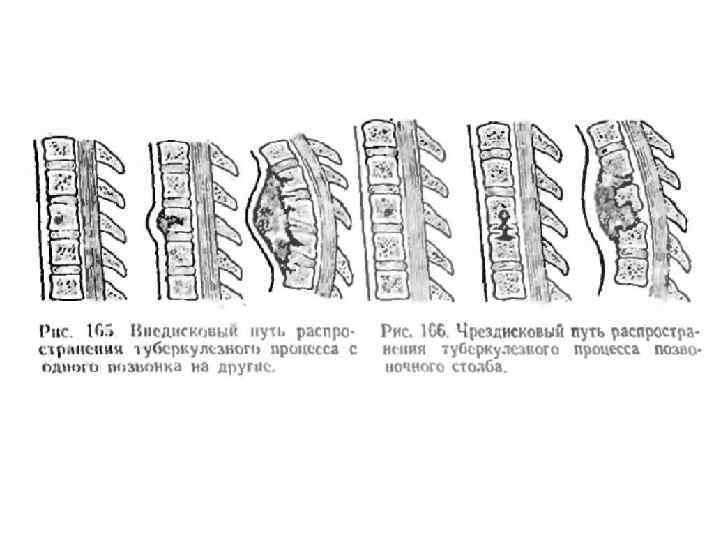

Туберкулёз позвоночника. Болеют чаще дети 10 -15 лет. Заболеванием поражаются 24 позвонка в грудном или поясничном отделе. В преспондилолитической фазе (процесс локализован в теле позвонка) имеются все признаки туберкулёзной интоксикации. Местная симптоматика отсутствует. На рентгенограмме выявляется очаг остеопороза и деструкции в теле позвонка.

Туберкулёз позвоночника. Болеют чаще дети 10 -15 лет. Заболеванием поражаются 24 позвонка в грудном или поясничном отделе. В преспондилолитической фазе (процесс локализован в теле позвонка) имеются все признаки туберкулёзной интоксикации. Местная симптоматика отсутствует. На рентгенограмме выявляется очаг остеопороза и деструкции в теле позвонка.

Спондилолитическая фаза • Спондилолитическая фаза (разрушение тела позвонка и переход процесса на межпозвонковые диски и окружающие мягкие ткани). • Кроме общих симптомов характеризуется появлением болей при наклоне туловища и ограничение движений из-за болей в позвоночнике. • При осмотре определяется искривление линии позвоночного столба, выступание остистого отростка, горб. • Для этой фазы характерен также "симптом вожжей" - напряжение мышц спины в виде тяжей, идущих от углов лопаток к поражённому позвонку. При надавливании на остистый отросток разрушенного позвонка пациент ощущает боль. • На спондилолитическом этапе туберкулёза позвоночника появляются натёчные абсцессы и свищи. Смещение тел позвонков может привести к сдавлению спинного мозга и развитию параличей конечностей, нарушениям функций тазовых органов. • На рентгенограмме определяется деструкция тел позвонков - признак патологического компрессионного перелома позвоночника, тени натёчных абсцессов.

Спондилолитическая фаза • Спондилолитическая фаза (разрушение тела позвонка и переход процесса на межпозвонковые диски и окружающие мягкие ткани). • Кроме общих симптомов характеризуется появлением болей при наклоне туловища и ограничение движений из-за болей в позвоночнике. • При осмотре определяется искривление линии позвоночного столба, выступание остистого отростка, горб. • Для этой фазы характерен также "симптом вожжей" - напряжение мышц спины в виде тяжей, идущих от углов лопаток к поражённому позвонку. При надавливании на остистый отросток разрушенного позвонка пациент ощущает боль. • На спондилолитическом этапе туберкулёза позвоночника появляются натёчные абсцессы и свищи. Смещение тел позвонков может привести к сдавлению спинного мозга и развитию параличей конечностей, нарушениям функций тазовых органов. • На рентгенограмме определяется деструкция тел позвонков - признак патологического компрессионного перелома позвоночника, тени натёчных абсцессов.

Туберкулез позвоночника • Постспондилолитическая фаза характеризуется стиханием воспаления. Однако натёчные абсцессы, свищи и нарушения иннервации сохраняются.

Туберкулез позвоночника • Постспондилолитическая фаза характеризуется стиханием воспаления. Однако натёчные абсцессы, свищи и нарушения иннервации сохраняются.